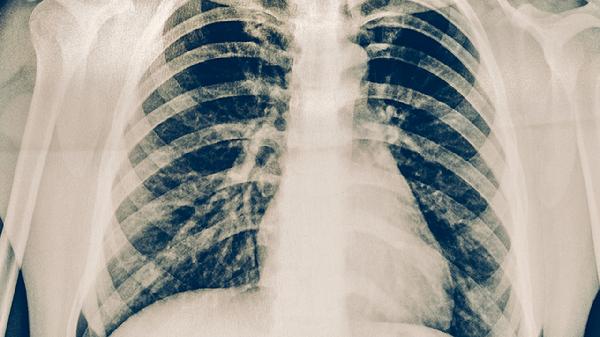

慢性肺炎患者可遵医嘱使用阿莫西林克拉维酸钾片、头孢克肟分散片、左氧氟沙星片、阿奇霉素片、盐酸莫西沙星片等消炎药。慢性肺炎可能与细菌感染、支原体感染、免疫功能低下等因素有关,通常表现为咳嗽、咳痰、发热等症状。建议及时就医,在医生指导下规范用药。